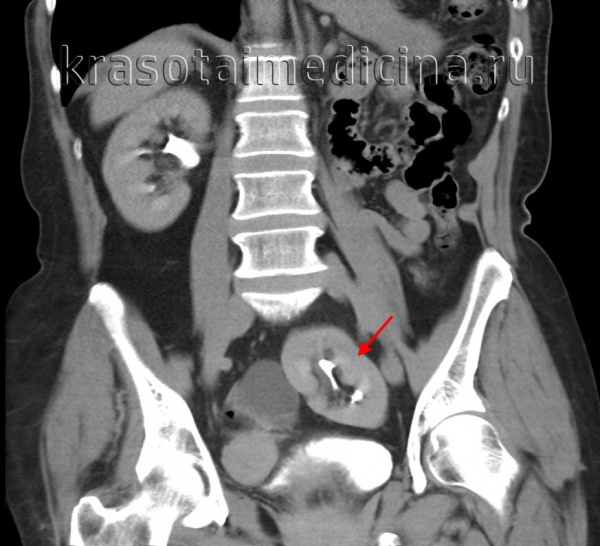

КТ, корональная реформация. Агенезия правой почки.

Тазовое расположение почки встречается с частотой 1 на 3000, что делает этот вариант одним из наиболее распространенных почечных эктопий. Обычно протекает бессимптомно. Хорошо определяется любым лучевым методом

Почка в форме пирога (дисковидная почка) встречается относительно редко. При этой аномалии верхний и нижний полюса почки слиты и обычно почка имеет 2 мочеточника. Сама эктопичная почка расположена впереди бифуркации аорты.